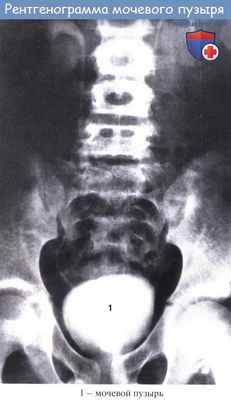

В мочевом пузыре различают верхушку, шейку, дно и тело. Верхушка - место перехода мочевого пузыря в среднюю пузырно-пупочную связку (заросший урахус). Дно — наиболее широкая нижнезадняя часть мочевого пузыря, обращенная у мужчин в сторону прямой кишки, у женщин — в сторону матки и верхней части передней стенки влагалища. Шейка - суженная часть мочевого пузыря, граничащая с мочеиспускательным каналом. Средний отдел, расположенный между верхушкой и дном мочевого пузыря, называется телом.

В наполненном мочевом пузыре различают переднюю, заднюю, верхнюю, правую и левую боковые стенки. На рентгенограммах нормальный мочевой пузырь, наполненный рентгеноконтрастным веществом, имеет овальную (у женщин) или шаровидную (у мужчин) форму и ровные четкие контуры. Нижняя граница мочевого пузыря обычно расположена на уровне верхнего края симфиза лобковых костей или немного ниже.

У новорожденных мочевой пузырь выступает над симфизом; с возрастом он постепенно опускается в малый таз. Емкость мочевого пузыря у новорожденных колеблется в пределах 50—80 мл, с возрастом он увеличивается. Емкость пузыря для каждого возраста определяется по формуле: 146 + (6,1 х возраст).